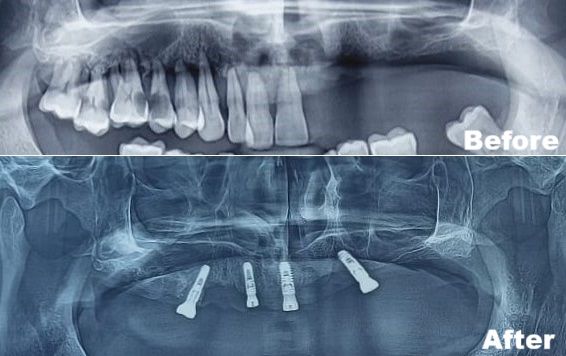

This article reports the full mouth rehabilitation of a 45-year-old male patient with grade 3 mobility in both upper and lower teeth due to chronic generalized periodontitis.

At Magadh Oro Dental, we decided to extract all teeth and restore his smile using:

This case highlights the efficiency of advanced implant protocols in restoring function and esthetics.